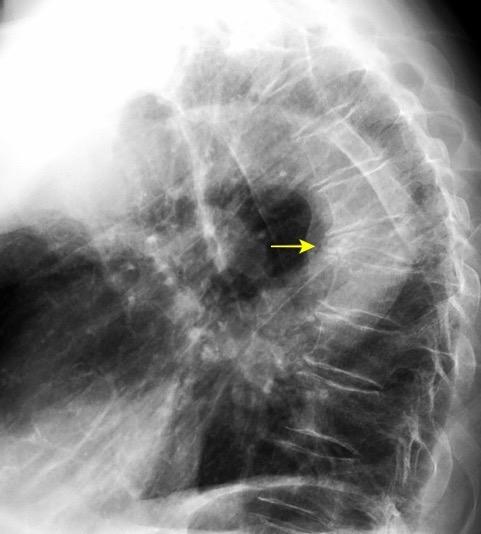

Raro. (2-9% de los T. tímicos). Asintomático. Contiene grasa (hasta 90%) y tejido timico (10-33%). Pueden ser muy grandes y confundirse con cardiomegalia. La tomografía “clásica” muestra los límites de la silueta cardiaca. (flechas)